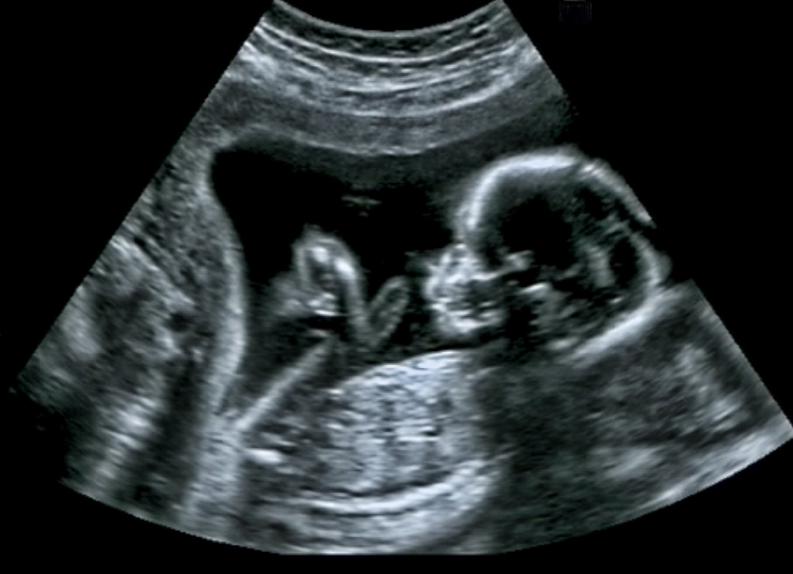

Medical ultrasound is a diagnostic imaging technique based on the application of ultrasound. It is used to create an image of internal body structures such as tendons, muscles, joints, blood vessels, and internal organs. Its aim is often to find a so